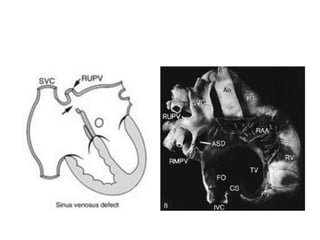

• Sinus venosus defects occur outside the margins

of the fossa ovalis, in relation to the venous

connections of the right atrium. They are located

posterior and superior to the fossa ovalis . Most

often, the defect is rimmed by atrial septal tissue

only anteroinferiorly. Its posterior aspect is the

right atrial free wall, and its superior border is

often absent because of an overriding superior

vena cava. Infrequently, the defect may be

directly posterior to the fossa ovalis or may be

posteroinferior such that the inferior vena cava

may join both atria